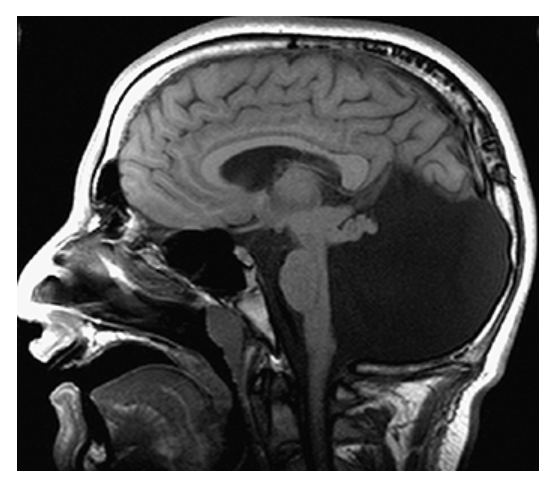

Agenesis of the Corpus Callosum. Sagittal T1W image shows congenital absence of the corpus callosum with radially oriented gyri and the absence of the cingulate gyrus.

Dandy-Walker Syndrome. Sagittal T1W image shows a massively dilated fourth ventricle, expanded posterior fossa, high-riding torcula, and hypoplastic cerebellum.